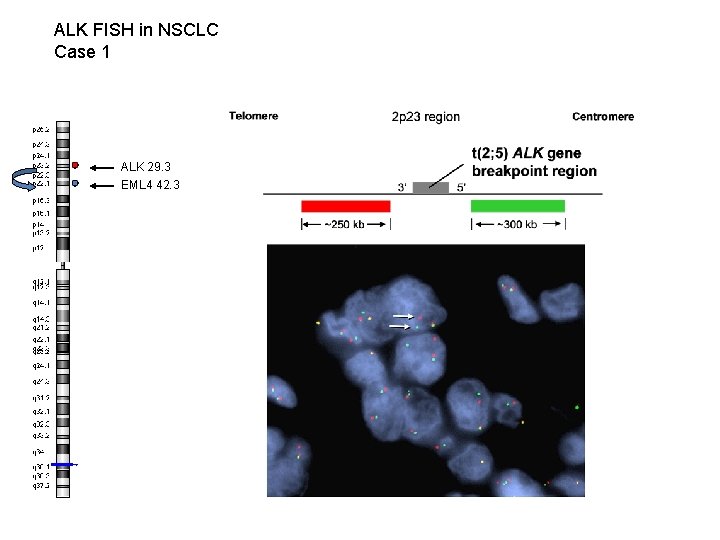

ALK FISH in NSCLC Case 1 ALK 29. 3 EML 4 42. 3 WT (non-split) signal Split signal